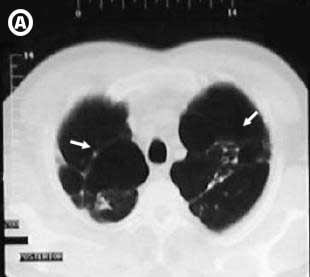

Corte Tomográfico

Corte tomográfico A, transversal a nivel de vértices pulmonares de aspecto lobulado con tabiques y ausencia de dibujo pulmonar en su interior, dichos tabiques en bandas o septus fibrosos que se extienden hasta la pleura parietal.

Corte tomográfico B, mas inferior donde observamos el aumento del espacio retro esternal ocupado por bula enfisematosa pulmonar izquierda.